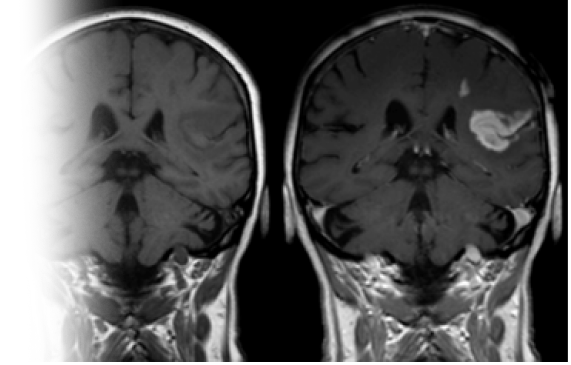

МРТ головного мозга с контрастом

Магнитно-резонансная томография головного мозга с контрастированием – важный метод исследования с введением контрастного вещестава, который позволяет визуализировать все структуры головного мозга (продолговатый мозг, мост, мозжечок, передний мозг) до и после контрастирования.